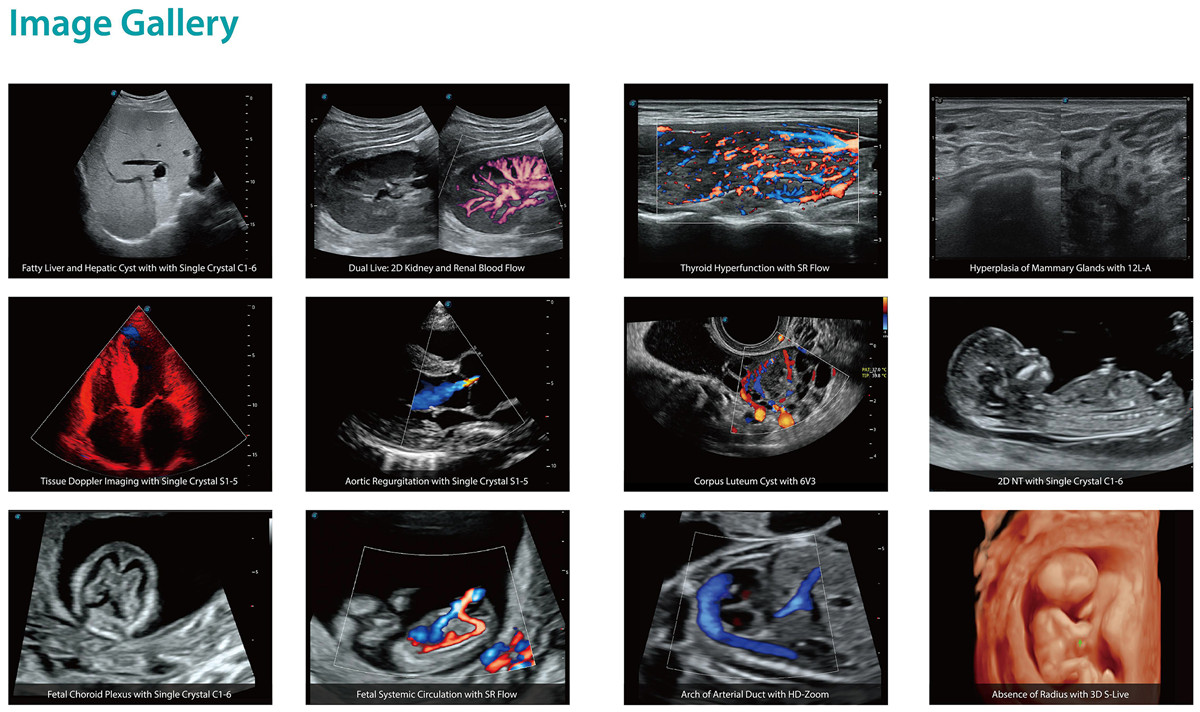

Monocristal Convex C1-6 / Sector S1-5

Els transductors d'un sol cristall permeten una imatge pura, especialment per a pacients difícils, augmentant la uniformitat de l'alineació del cristall i augmentant l'eficiència de la transmissió d'energia.Single Crystal C1-6 per a pacients abdominals i OB i S1-5 per a aplicacions de cardiologia i transcranials.

Transductor lineal de cristall compost

Mitjançant la reforma dels materials piezoelèctrics convencionals, els transductors de cristall compost aconsegueixen un millor espectre acústic i una impedància acústica més baixa per servir bé en vascular, mama, tiroides, MSK, etc. La combinació de 12L-A, 12L-B, 9L-A cobreix un ultra -amplada de banda de freqüència àmplia, gairebé sense punt cec per a tot tipus d'escaneig.

Volum elaborat ultralleuger VC2-9

El VC2-9 adopta un disseny senzill però potent, que no només proporciona una millora notable en la qualitat de la imatge 3D/4D, sinó que també redueix el pes per si mateix per a una adherència més còmoda mentrestant.L'amplada de banda ultraamplia, la resolució exquisida i la penetració a un volum elevat fan que VC2-9 sigui una solució d'una sola sonda durant gairebé tot l'embaràs.